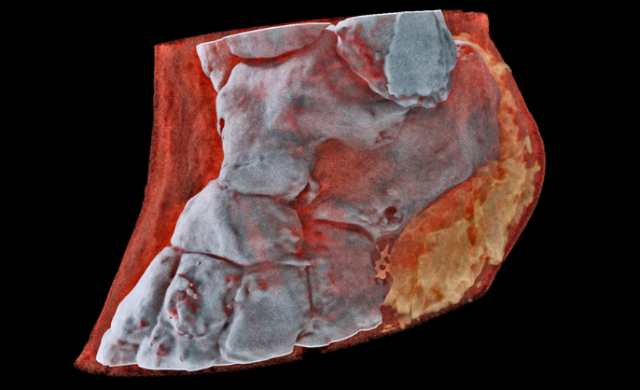

Медики впервые сделали рентген костей человека с трехмерными цветными изображениями. А примеры получившихся снимков можно увидеть на сайте новозеландской компании MARS Bioimaging.

Технологию придумали в семье ученых Батлер: отец работает физиком в университете Кентербери, а сын — рентгенолог в университетах Отаго и Кентербери. Основа рентгена в специальных детекторах с мощным энергетическим разрешением. Вообще они создавались для адронного коллайдера, но Батлеры приспособили их для медицинских целей.

«Сканеры MARS делают снимки, на которых можно различить мягкие ткани, жир и кости», — пишут ученые.

В первый раз цветной рентген протестировали на одном из его создателей — Филу Батлеру просканировали лодыжку и запястье. Теперь разработчики проведут клиническое исследование, в рамках которого врачи будут использовать и сравнивать новое и старое оборудование.